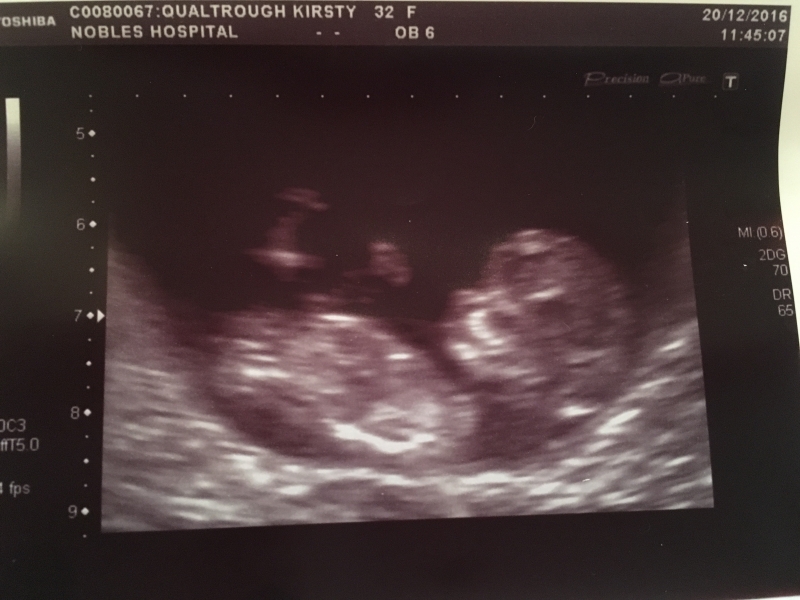

What a month! Along with the usual run-up to Christmas festivities (mince pie making, winter walks with Mum and Lass, Christmas shopping and wrapping) we had the added enjoyment/excitement of having our first baby scan!! On 20th December we went to Nobles for an ultrasound where we saw our little one for the first time - moving around in it's little uterus play-pen! It was a really amazing moment seeing it on the screen for the first time, confirming the reality of us becoming parents in just over 6 months time! The sonographer was able to tell us that I was 11 weeks 3 days along, with a due date of 8th July 2017 Once we had the scan pictures we broke the news to the family over the next few days (having already told my Mum on the day she came back from New Zealand!). I would say that Christmas this year was a fairly chilled event - to be honest I didn't have the usual energy or motivation....and not being able to share in the fizz/beer/wine/port made things slightly more low key (yet healthier!) than other years! But it was really nice to be able to chill (I stayed at mum's from 22-26th and then at Glenn's for a few days while Max and Zoe were over), play games, take naps, eat when I liked (which I did a lot of!) and be as energetic as I liked 🙂 While at mum's we got out for plenty of nice walks up in the hills and played games in front of the fire, and at Margie's we also played games, ate lots of roasts and had a trip out to hunt for wallabies 🙂 New Year's Eve was also a quiet affair - we went down to the Duggan's for the buffet and chit chat and joined the family for part of the pub crawl (even though it was windy and wet!) to the Bay, Falcs and Station before we retired back to Failt Erriu (about 10.30pm) where we chilled with Mum and welcomed 2017 in with hugs and excited expectations for the year to come. After a lovely Christmas break it was nice to get back to the flat, clear away the Xmas tree and deccy's and get back into some sort of 'normal' routine (for a while at least!). We've got more midwife appts and scans happening over the next few months, and lots of decisions to make about work/living etc so watch this space for updates! Here's a few pics from over the Christmas period: